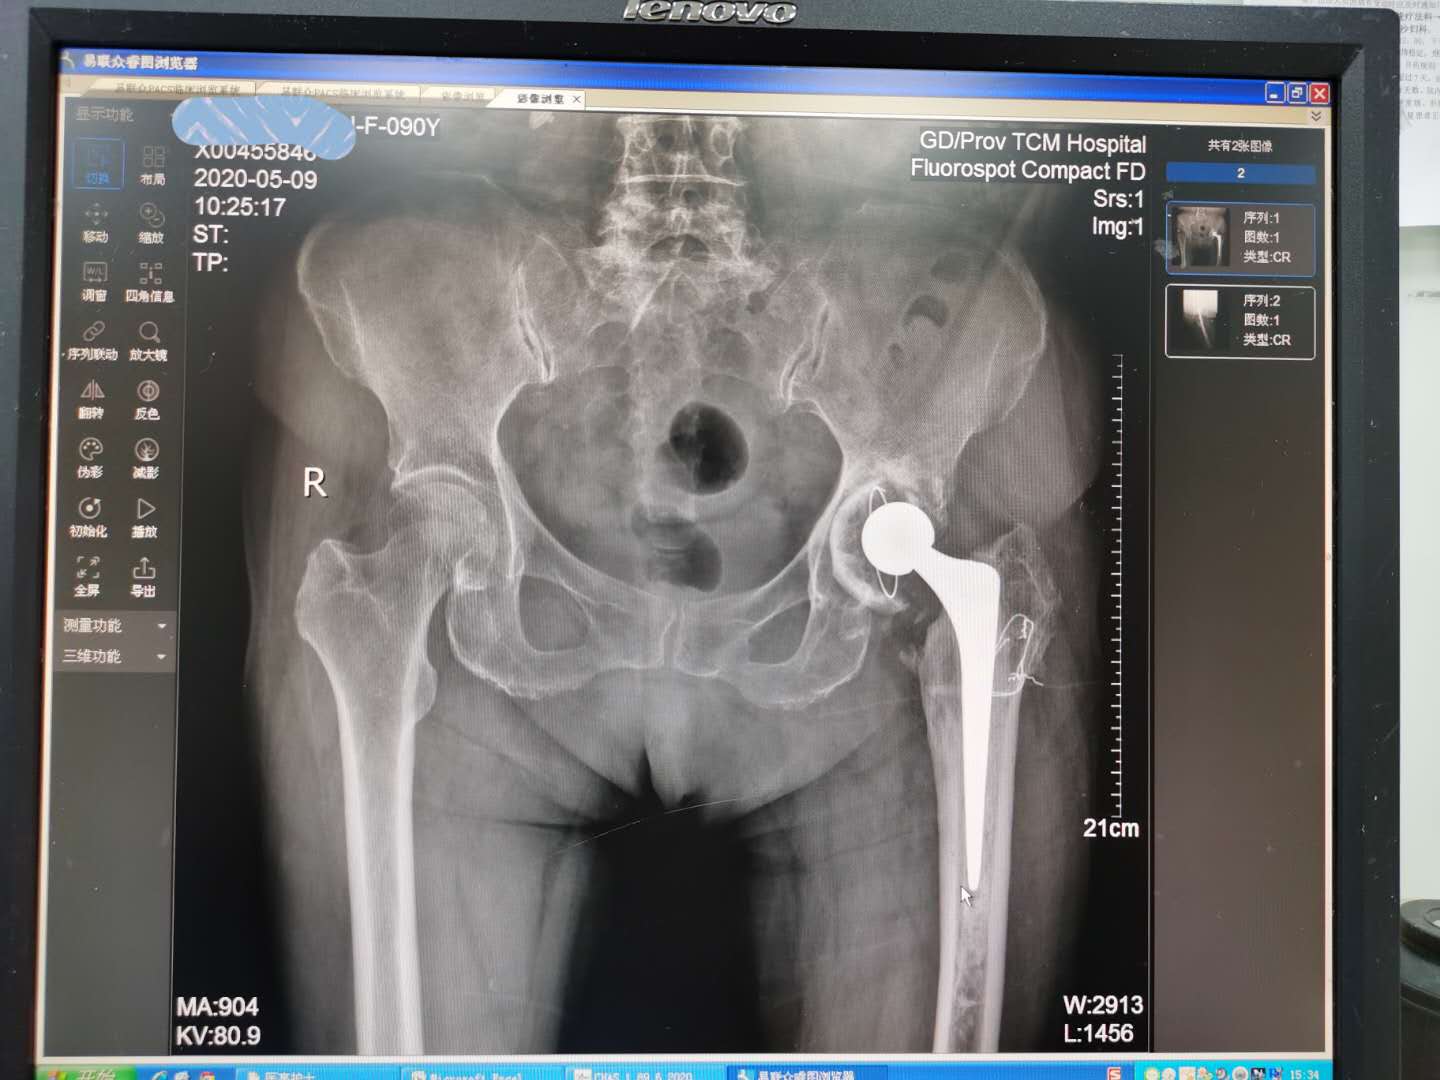

1998年这位老人家因为跌倒左股骨颈骨折,当时诊治的骨科医院处理不佳,术后一年多出现了左髋疼痛的现象,于2001年来到了我院治疗,检查提示“左股骨颈骨折术后,左股骨头坏死”,随后进行了左股骨骨折内固定拆除术+左全髋关节置换术。术后恢复良好,顺利出院,老人家左髋疼痛消失,跛行的现象也消失了,之后身体也不错。

如今19年过去了,老人家因为左髋疼痛半年才来到了医院。入院体查:左大腿后外侧可见一长约15cm左右陈旧性手术疤痕,愈合良好。左侧腹股沟、大粗隆外侧、髋关节后方压痛(+),髋关节屈曲、后伸、外展活动受限,左下肢无明显短缩,肢端感觉、血运可。

入院中医诊断:痹症(肝肾亏虚,气滞血瘀);西医诊断:1.左髋关节置换术后疼痛;2.左髋关节假体松动;3.骨质疏松;4.高血压3级(很高危组);4.手术史(左侧全髋关节置换术)